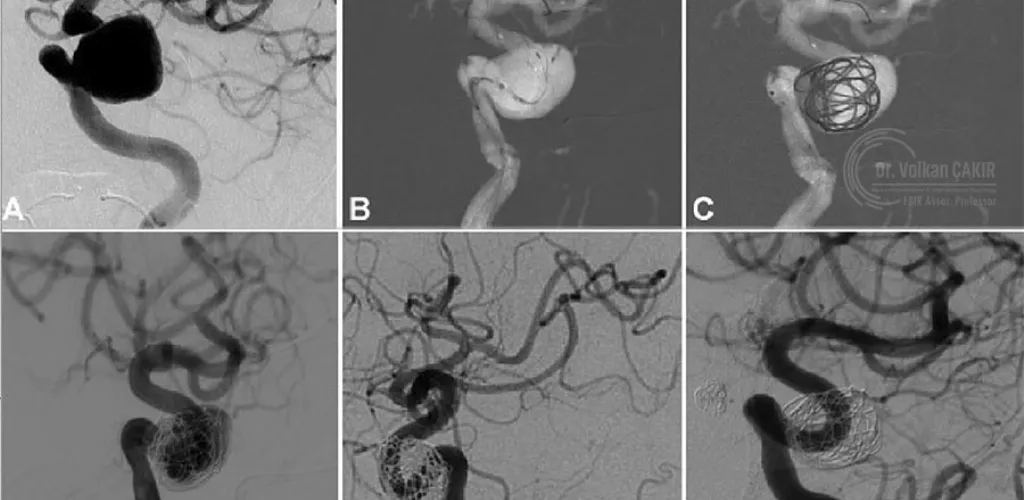

Endovascular Treatment for Complex Intracranial Aneurysms Ajman

Endovascular therapy is an advanced, image-guided procedure performed by a neurointerventional radiologist. Through a small puncture—usually in the groin or wrist—a microcatheter is carefully navigated through the vascular system to reach the aneurysm in the brain.

Using real-time, high-resolution imaging, specialized devices such as coils, stents, and flow diverters are precisely deployed to seal off the aneurysm from circulation. This prevents rupture and significantly reduces the risk of subarachnoid hemorrhage and stroke.

Endovascular techniques, including flow diversion and coil embolization, have transformed the management of complex intracranial aneurysms. These procedures are now considered first-line treatments in many cases due to their safety profile and effectiveness.